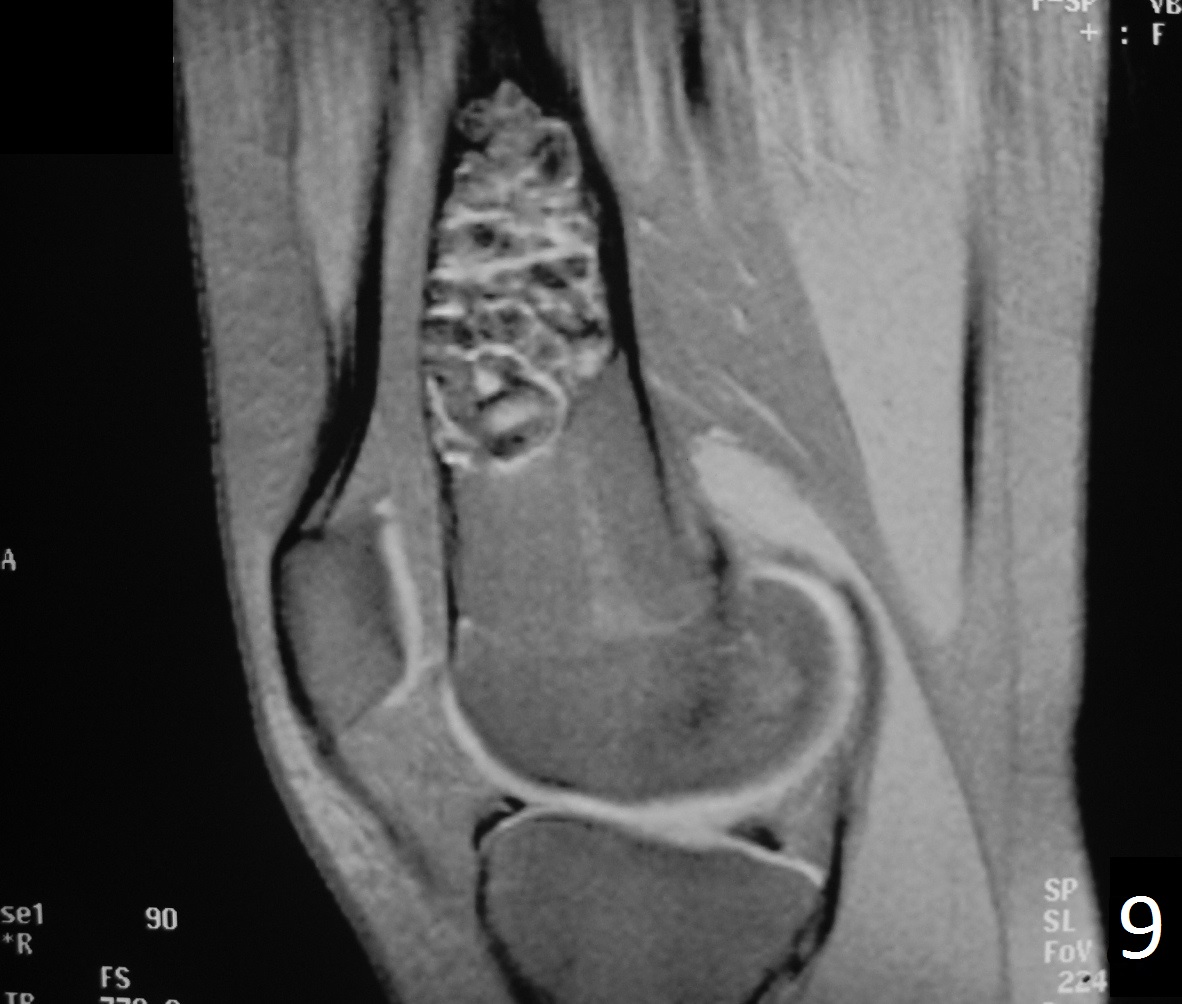

From www.pinterest.cl

Nonossifying fibroma distal femur Radiology Case Radiology Non Ossifying Fibroma It is estimated that 30 to 40% of people under the age of 20 have an nof, although few will. Nonossifying fibroma is a common benign finding encountered in the practice of radiology. However, prophylactic curettage and bone grafting. Nonossifying fibromas (nofs) are the most common benign (not cancerous) bone tumor in children. Fibroxanthomas can be divided into: It is. Radiology Non Ossifying Fibroma.